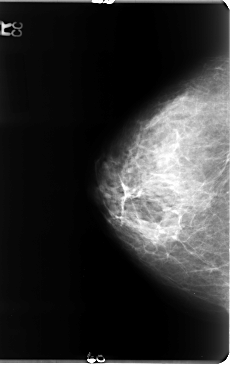

B_3072_1.LEFT_MLO

LEFT_MLO LINES 4656 PIXELS_PER_LINE 3016 BITS_PER_PIXEL 12 RESOLUTION 50 OVERLAY